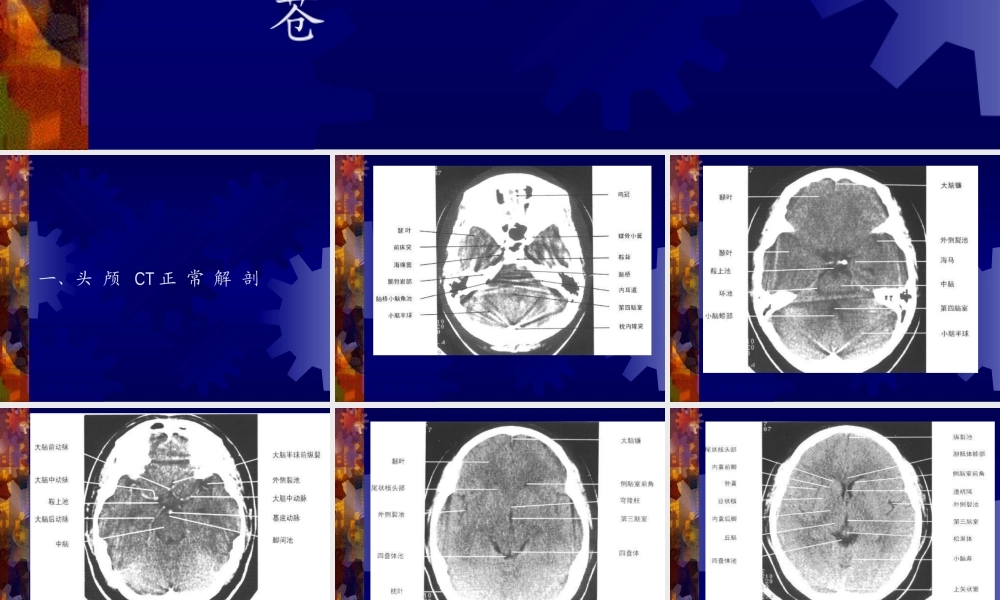

正常头颅CT及MRI解剖闫炳苍一、头颅CT正常解剖二、正常头颅MRI解剖三、脊柱的正常MRI解剖